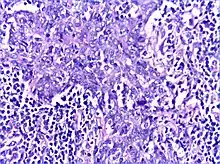

Histology

There is a marked lymphoplasmacytic infiltration. Lymphoid follicles surround solid epithelial nests, giving rise to the 'epimyoepithelial islands', that are mainly composed of ductal cells with occasional myoepithelial cells. Excess hyaline basement membrane material is deposited between cells, and there is also acinar atrophy and destruction.